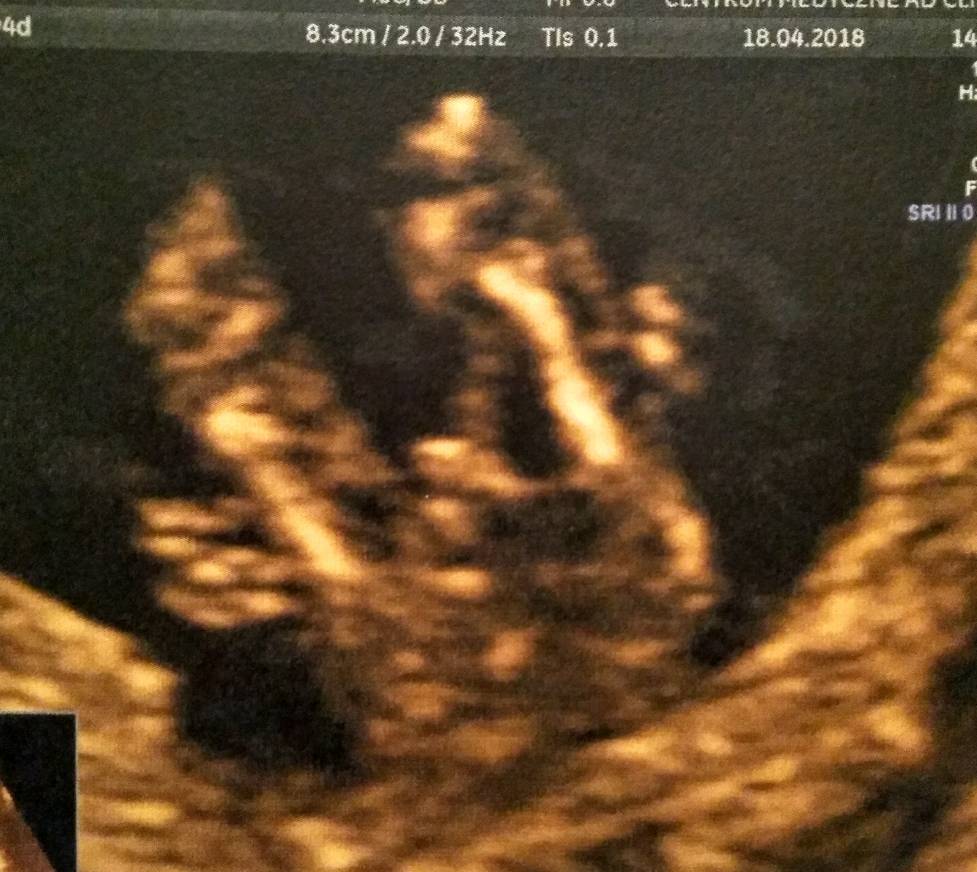

Zobacz załącznik 850251

zdjęcie z 12+4

Zobacz załącznik 850284